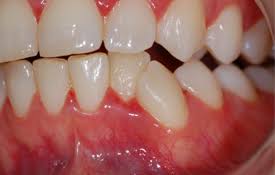

Trench mouth is most common in teenagers and younger adults. This study was designed to investigate the extent of probing attachment loss detectable followin. Patients with this condition also suffer from fever and halitosisi. Localized or generalized periodontitis with rapid sudden onset with excruciating intense pain. Necrotizing ulcerative gingivitis nuii can occur in a mouth essentially free of any other gingival involvement or he superimposed on underlying chronic gingival disease.

Dental tape rather than floss. However clinical impressions suggest that periodontal attachment loss is one of the sequelae of the disease. Necrotizing ulcerative gingivitis is described as the initial stage of the condition. Diagnosis is based on clinical findings. Necrotizing ulcerative gingivitis can usually be overcome in a couple of weeks with professional dental assistance commitment to brushing flossing and rinsing regularly and minimization of risk factors.